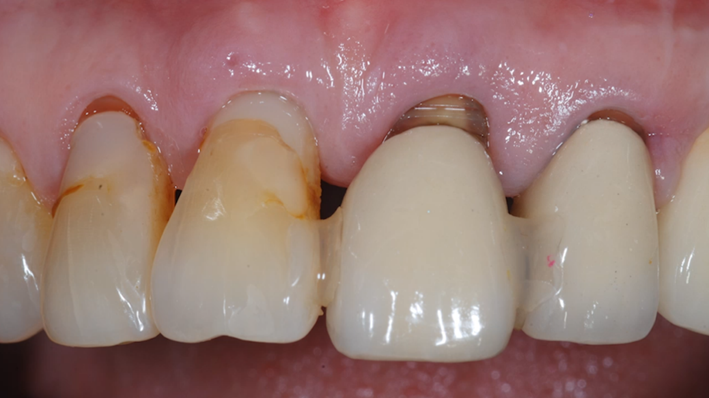

“ One implant /One tooth/ One hour step-by-step

+ associated connective graft ”

Clinical case: EImmediate implant placement & loading of #35 extraction socket with defect

- Courtesy of Dr. Kwang Bum Park, Korea -

Dr. Laurent Sers, immediate loading, digital guided surgery, digital ONE-DAY implant, maxillary anterior, #21, guided surgery, immediate loading, AnyRidge, R2GATE, Mega ISQ, R2GATE Full Surgical Kit

implant system, R2GATE Guide, R2GATE surgical kit (AnyRidge), Mega ISQ